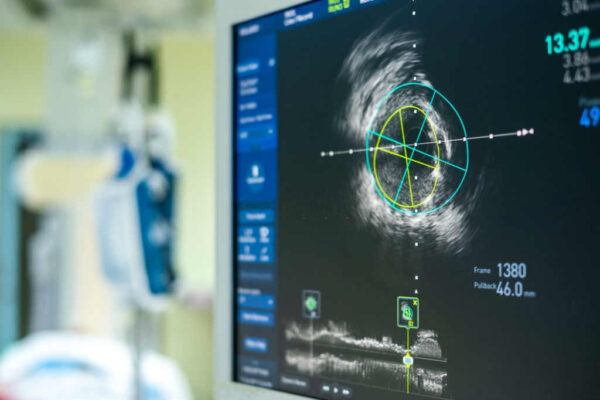

ما هي قسطرة القلب؟

- تستخدم قسطرة القلب لتشخيص وعلاج أمراض القلب والأوعية الدموية.

- أثناء القسطرة ، تساعد صور الأوعية (مقاطع فيديو الأشعة السينية) وتسجيلات الضغط والقياسات الأخرى طبيب القلب في التحقق من مرض الشريان التاجي وأمراض صمامات القلب وأمراض القلب الخلقية ، وحالات مرضية أخرى.

- تعد قسطرة القلب أحد أكثر الإجراءات فائدة لإعطاء الطبيب صورة واضحة عن صحة القلب بشكل عام.

كيف يتم عمل القسطرة بواسطة طبيب القلب والأوعية الدموية؟

- يتم إدخال أنبوب رفيع طويل يسمى القسطرة في شريان أو وريد في الفخذ أو الرقبة أو الذراع ويتم تمريره عبر الأوعية الدموية إلى قلب المريض .

- بمجرد وضع القسطرة يمكن قياس ضغط الدم في غرف القلب المختلفة ، ويمكن أخذ عينات الدم ، ويمكن تصوير الأوعية الدموية عن طريق حقن الصبغة (مادة تباين التصوير الشعاعي للسماح برؤية أفضل للقلب والأوعية الدموية بالأشعة السينية.

- بعض علاجات أمراض القلب مثل دعامة الأوعية التاجية تُجرى أيضًا باستخدام قسطرة القلب.